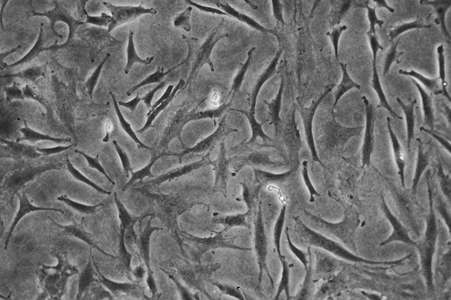

Augmentation of joint tissue homestasis

We investigate the effects of compounds normally found in plants and consumed in the diet, (dietary phytochemicals and their metabolites), and their effects on chondrocytes and synovial fibroblasts during inflammation. Our early work focussed on a compound commonly found in brassicas called sulforaphane and described a mechanism by which it can regulate NFkB signalling in models of osteoarthritis (OA). This work progressed from laboratory models to experimental medicine where we showed that through the diet, this compound can reach the target tissues of the joint in OA patients and significantly alter the synovial fluid proteome. More recently we have designed a feasibility trial to test dietary compounds for impacts on joint pain and function in OA patients.

We are developing automated, molecular workflows to identify phytochemical and/or metabolite bioactivity in cell models of inflammation at scale. We use multifactorial testing to identify synergistic interactions between phytochemicals within whole foods and from multiple sources, both common and rare in the habitual diet and across chemical classes. DISCOVER enables us to identify and interrogate dietary phytochemical bioactivities, molecular mechanisms and interactions across in vitro models of inflammation, to improve translation of data coming from lab models into humans.

Dupuytren’s Disease (DD) is a fibroproliferative disease that manifests in the palmar fascia, and over time, causes one or more digits to irreversibly contract toward the palm. Depending on the severity of contraction this can significantly impact hand function. Matrix metalloproteinase 14 (MMP14) is associated with DD severity and recurrence as are several SNPs. We are investigating the role of SNPs associated with DD using in vitro cell modelling methods.